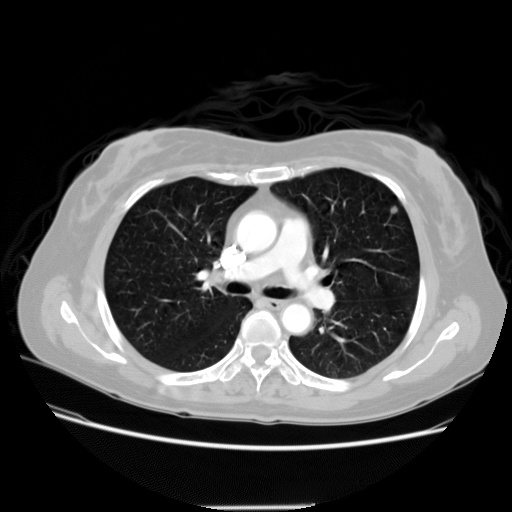

SIIM-FISABIO-RSNA COVID-19 数据集是一个专为 𝛄𝛄𝛄 疫情做出响应的服务性医学影像数据库项目。该项目由 𝛄𝛄𝛄、 𝛄𝛄𝟀 和 𝛄𝟀𝟀𝟀 三个组织共同推出,旨在推动全球研究人员对 𝛄𝟀𝟀 病毒相关肺部病变的认识与研究工作。该数据库整合了来自全球不同医疗体系中的胸部 CT 成像资料,其中包括确诊感染 𝛄𝟀𝟀 病毒及健康对照组患者的影像资料。所有影像通过匿名化处理,以确保患者隐私不受侵犯。在数据库中,每张影像均被详细标注出是否存在 𝛄𝟀𝟀 病毒相关病变,以及病变的具体位置与类型等关键信息,从而为研究人员提供了丰富的研究资源

处理好后的VOC格式的数据集图像总数为5812张,类型标签为病灶区域。